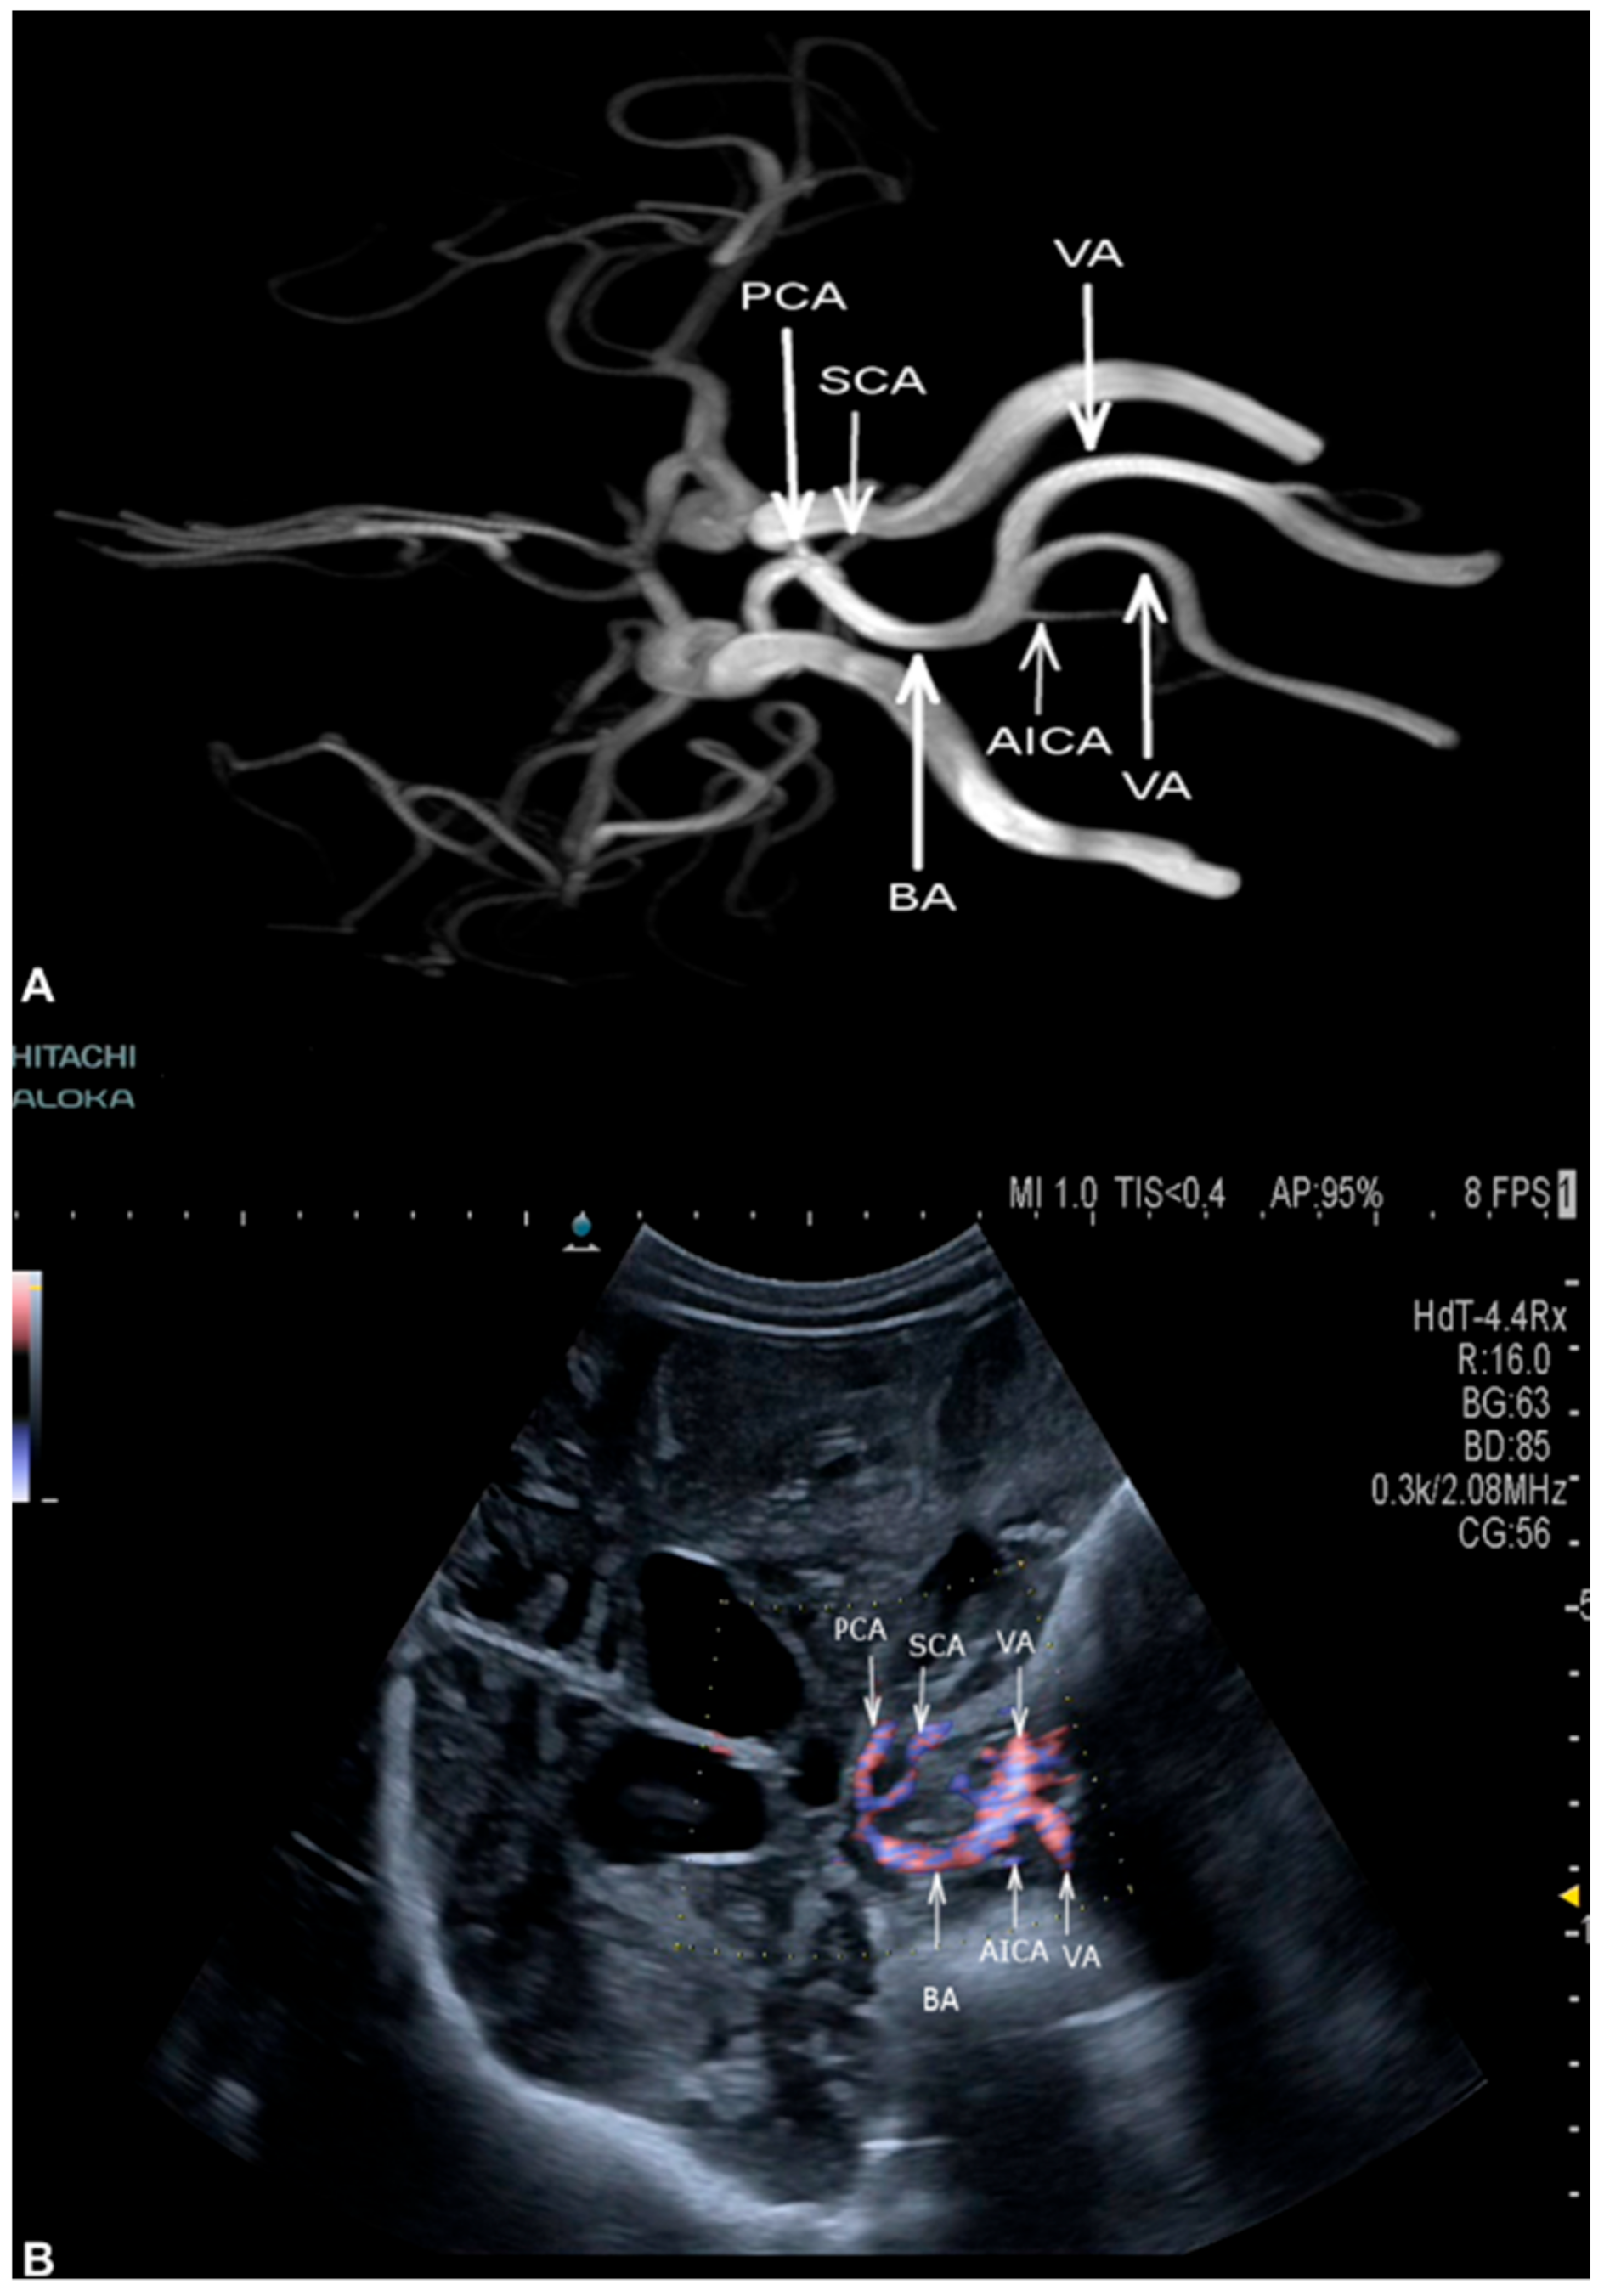

3.2. Cerebral Arteries